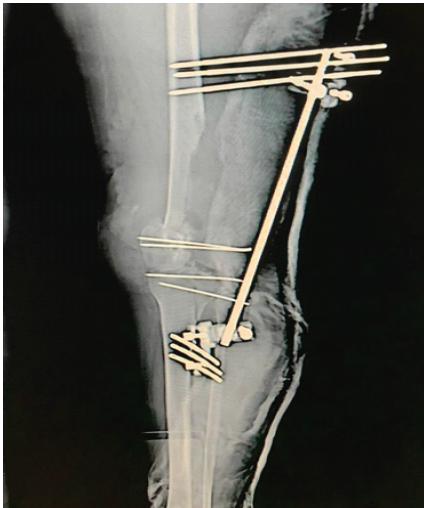

Emergency surgery was performed with irrigation, debridement, and insertion of a spanning external fixator connecting the tibial shaft to the femoral shaft (Fig. 2).

Figure 2: Initial management with a knee-spanning external fixator following irrigation and debridement.

Three screws were inserted into the distal femur connecting the medial and lateral condyles, and another three screws into the proximal tibia, connecting the medial and lateral tibial plateaus.

The knee was immobilized in extension. The patient received IV antibiotics and underwent serial dressings. Over 6 weeks, the wound healed, inflammatory markers normalized, and there were no signs of infection.